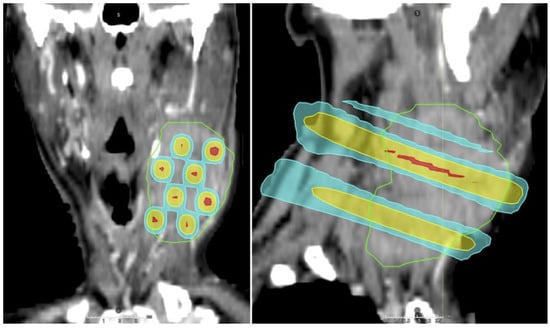

6. Spatially Fractionated Radiotherapy

- At, B.; Velayudham, R. Assessing dosimetric advancements in spatially fractionated radiotherapy: From grids to lattices. Med. Dosim. 2024, 49, 206–214. [Google Scholar] [CrossRef]

- Li, H.; Mayr, N.A.; Griffin, R.J.; Zhang, H.; Pokhrel, D.; Grams, M.; Penagaricano, J.; Chang, S.; Spraker, M.B.; Kavanaugh, J.; et al. Overview and Recommendations for Prospective Multi-institutional Spatially Fractionated Radiation Therapy Clinical Trials. Int. J. Radiat. Oncol. Biol. Phys. 2024, 119, 737–749. [Google Scholar] [CrossRef]